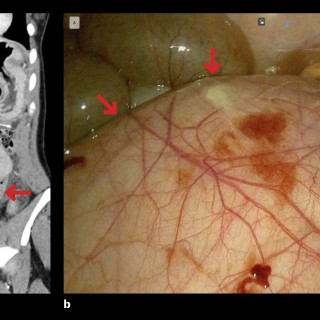

Kasuistikken beskriver en pasient med cystisk ekinokokkose og behov for omfattende kirurgisk behandling. Tilstanden er sjelden i Norge, men utgjør et betydelig folkehelseproblem globalt. På grunn av økende innvandring fra høyendemiske land, bør norske leger kjenne til denne zoonosen. En tidligere frisk mann i 40-årene, oppvokst i Midtøsten og bosatt i Norge de siste årene, ble akutt innlagt på medisinsk avdeling ved lokalsykehuset, etter to døgn med respirasjonsavhengige smerter i høyre hemitoraks. I forkant av innleggelsen hadde han hatt fem ukers sykehistorie med høyresidige flankesmerter...